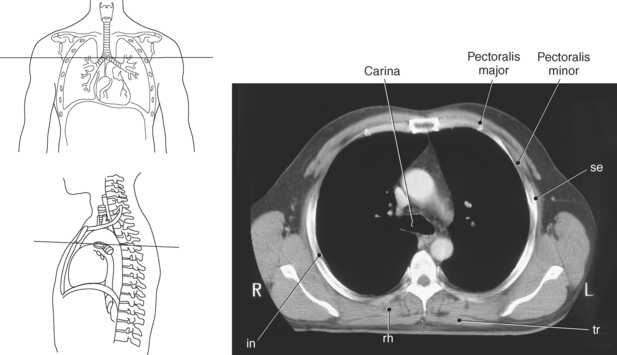

Muscles associated with respiration are the intercostal, serratus posterior superior, serratus posterior inferior, and the diaphragm (Table 6.3). The spaces between the ribs, or the intercostal spaces, are filled with three layers of intercostal muscles (external, internal, and innermost layer) (Figures 6.106 through 6.108). These muscles act together to elevate the ribs and expand the thoracic cavity, as well as keep the intercostal spaces somewhat rigid. The serratus posterior superior muscle spans from C7-T2 to ribs 2 to 5 and acts to assist forced inspiration, whereas the serratus posterior inferior muscle spans from T11-L2 to ribs 9 to 12 and acts to assist forced expiration (Figures 6.109 through 6.110). The diaphragm is a large dome-shaped muscle that spans the entire thoracic outlet and separates the thoracic cavity from the abdominal cavity (Figure 6.111). It is the chief muscle of inspiration because it enlarges the thoracic cavity vertically as the domes move inferiorly and flatten. The muscle fibers of the diaphragm converge to be inserted into a central tendon, which is situated near the center of the diaphragm immediately below the pericardium, with which it is partially blended. The diaphragm is attached to the lumbar spine via two tendinous structures termed crura (Figures 6.111 through 6.113). The right crus arises from the anterior surfaces of L1-L3, whereas the left crus arises from the corresponding parts of L1-L2 only. The left and right crura join together across the ventral aspect of the abdominal aorta to form the medial arcuate ligament. Three major openings, or hiatuses, of the diaphragm allow for the passage of vessels and organs from the thorax to the abdomen. The aortic hiatus allows for the passage of the descending aorta, azygos vein, and thoracic duct. The caval hiatus allows for the passage of the inferior vena cava and the right phrenic nerve. The esophageal hiatus allows for the passage of the esophagus and the vagus nerve.

Figure 6.110 Axial CT scan of chest with serratus posterior superior muscle.

Key: se, Serratus posterior superior; tr, trachea; rh, rhomboid muscle; in, intercostals; ts, transversospinal muscles; tra, trapezius muscle.